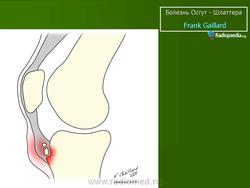

Характеризуется наличием боли и припухлости в месте прикрепления сухожилия надколенника к болылеберцовому бугорку. Общей симптоматики нет.

На рентгенограмме выявляются признаки фрагментации бугорка болылеберцовой кости.

На рентгенограмме отек мягких тканей, утолщение хряща, покрывающего бугристость спереди, фрагментация бугристости

Над бугристостью большеберцовой кости появляется припухлость, отечность, утолщение и выбухание хряща, болезненность при пальпации, а также при опоре на коленный сустав, в момент сгибания и выноса конечности кпереди.

В оценке рентгенологических признаков болезни Шлаттера необходимо учитывать большое число вариантов нормальной оссификации апофиза большеберцовой кости, разный ее характер справа и слева [Рейнберг С. А., 1964; Радулеску А., 1967]. Поэтому диагностику основывают на данных клиники (боль, припухлость) и несоответствии между значительным выбуханием хряща бугристости и меньшей ее величиной на рентгенограмме.